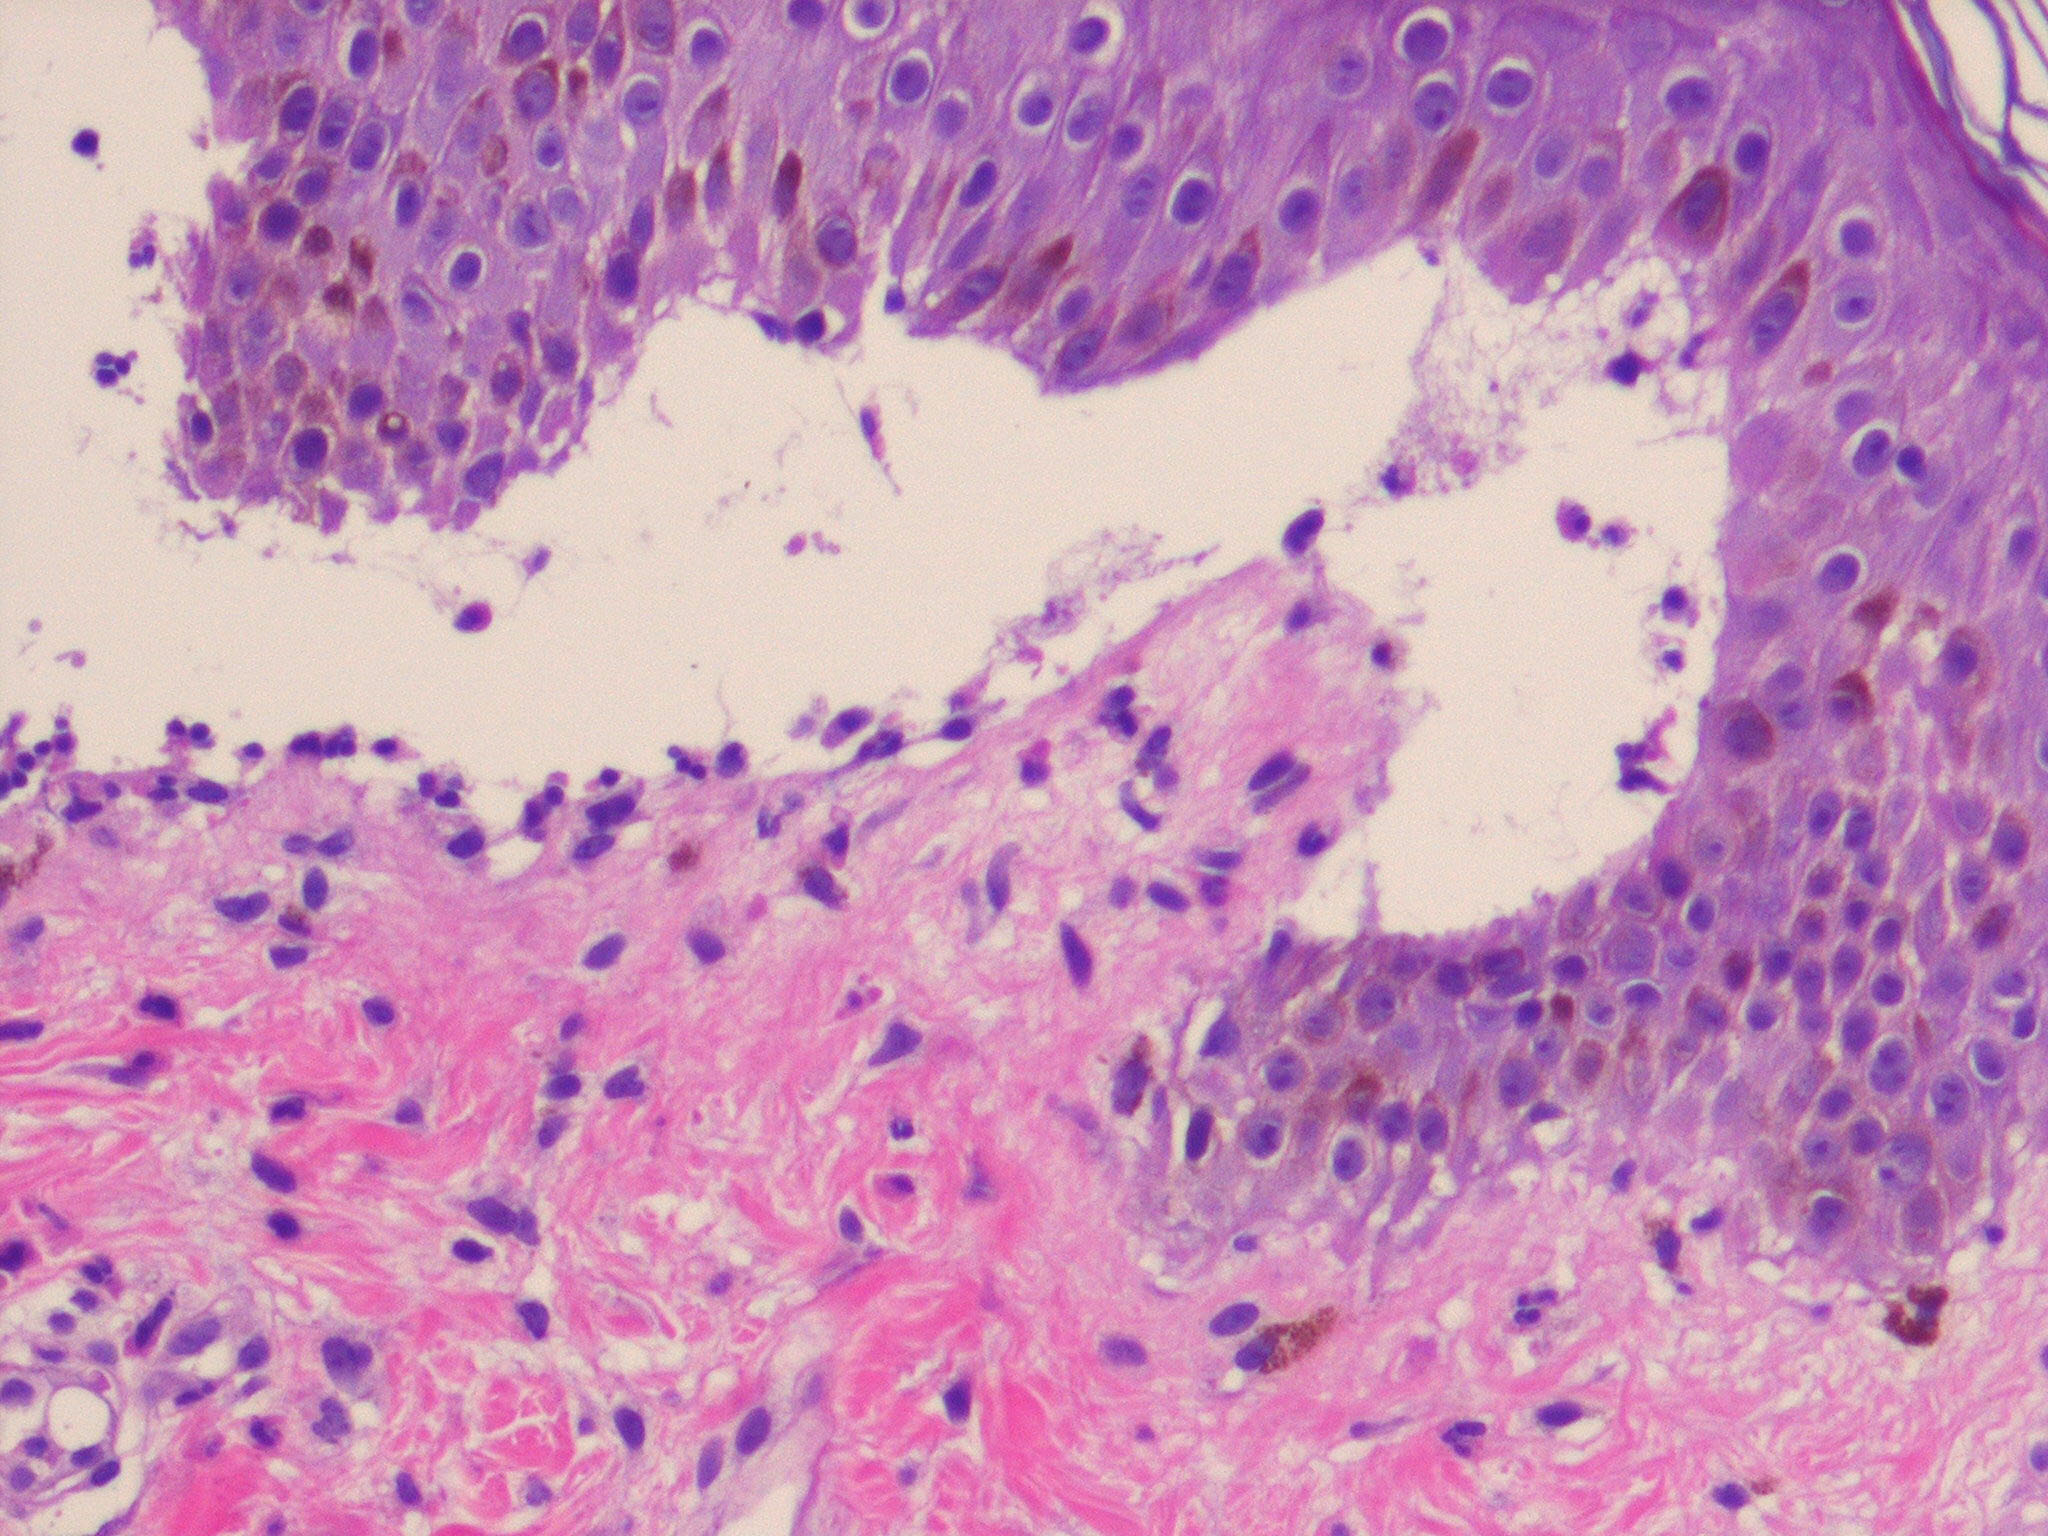

Histologically, the lesions of bullous impetigo show vesicle formation in the sub-corneal or granular region, occasional acantholytic cells within the blister, spongiosis, edema of the papillary dermis, and a mixed infiltrate of lymphocytes and neutrophils around blood vessels of the superficial plexus.